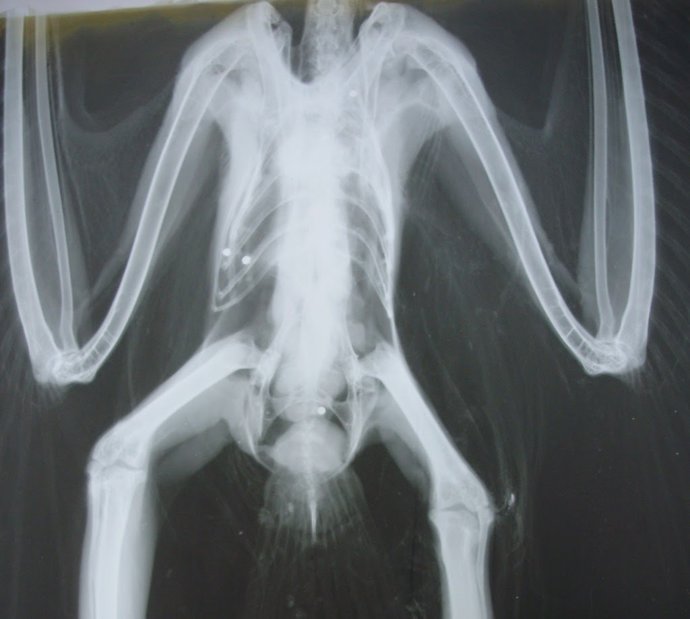

Archivo - Radiografía de un ave con perdigones de plomo

Archivo - Radiografía de un ave con perdigones de plomo - SEO/BIRDLIFE - Archivo